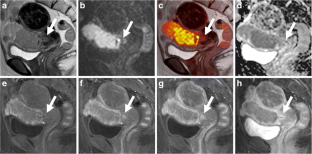

Fig. 2